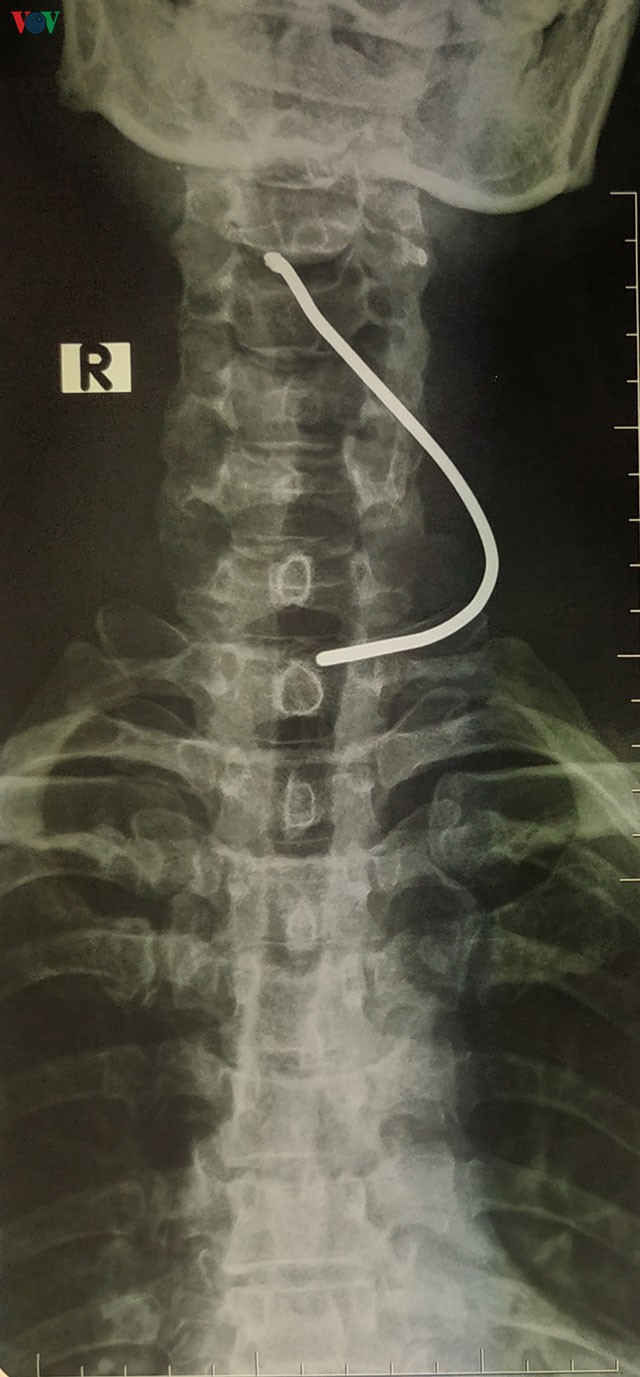

Phim chụp Xquang.

Một người đàn ông 50 tuổi ở Sơn Lôi, tỉnh Vĩnh Phúc đang ngồi sửa xe máy trước cửa nhà thì bất ngờ bị một thanh sắt găm vào cổ.

Tai nạn xảy ra khi chiếc xe ô tô tải ngang qua đó, bất ngờ bị nổ lốp tạo áp lực khiến thanh sắt đang nằm trên đường bắn vào cổ nạn nhân.

Người bệnh được chuyển đến bệnh viện đa khoa tỉnh Vĩnh Phúc trước khi chuyển viện đến Bệnh viện Hữu nghị Việt Đức. Vùng cổ của bệnh nhân có vết thương thanh quản 0,5cm gây tổn thương sụn giáp, may mắn không tổn thương dây thanh âm nên không ảnh hưởng đến chức năng giọng nói.

Thạc sĩ, bác sĩ Dương Ngọc Thắng, Trung tâm Tim mạch và Lồng ngực, Bệnh viện Hữu nghị Việt Đức đã tiến hành phẫu thuật thăm dò vết thương cho bệnh nhân, lấy dị vật và khâu vết thương sụn giáp. Sau ca mổ, sức khỏe bệnh nhân ổn định và đã được xuất viện sau 3 ngày điều trị./.